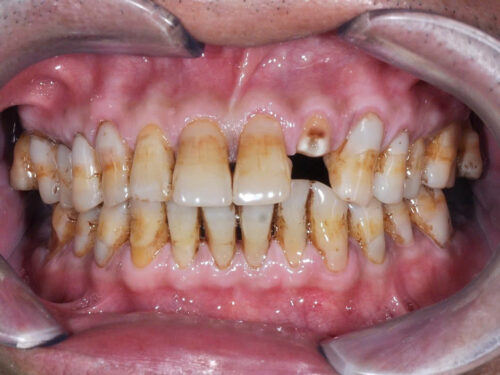

Ca lâm sàng: (PBL) bệnh nhân nam 60 tuổi đến với tình trạng răng 22 gãy thân răng ngang lợi. Bệnh nhân được tiến hành điều trị tủy răng 22 và đặt chốt đúc để tạo điểm lưu giữ cho phục hình chụp toàn sứ thay thế phần thân răng đã mất.